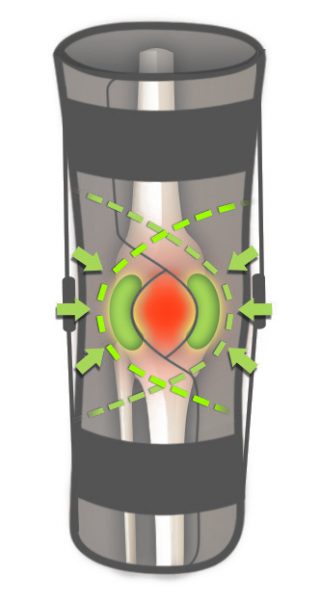

Każda orteza z serii IB jest wyposażona w dwie wyprofilowane peloty, które wzmacniają i stabilizują rzepkę.

Każda orteza z serii IB jest wyposażona w dwie wyprofilowane peloty, które wzmacniają i stabilizują rzepkę.